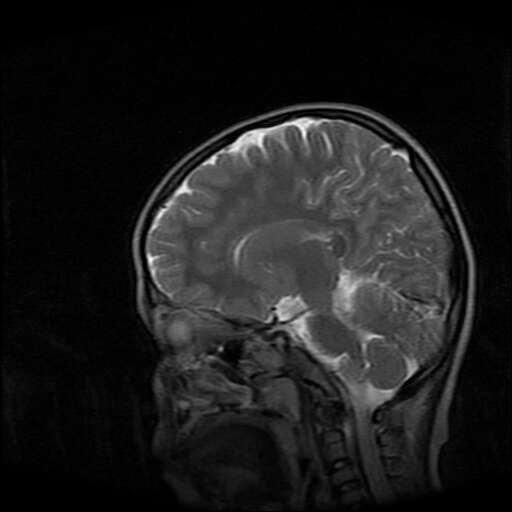

女,7岁,三岁才说话、走路。现智力尚可,走路不稳。临床怀疑大脑发育不全。

脑折质变薄,双侧侧脑室稍扩张,支持考虑脑折质发育不良

考虑胼胝体发育不全,髓鞘形成不良。

支持考虑胼胝体发育不全,髓鞘形成不良。

脑裂畸形伴灰质异位

侧脑室周围白质数量减少,侧脑室不对称性扩大,左侧侧脑室后角呈方形改变,脑沟加深,结合临床考虑脑室周围白质软化症(pvl)。期待结果!